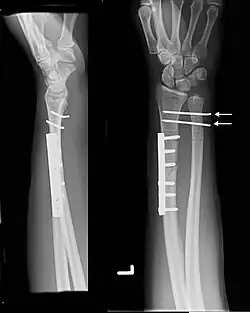

| Galeazzi fracture. Arrow points at the dislocated ulnar head | |

The Galeazzi fracture is a fracture of the distal third of the radius with dislocation of the distal radioulnar joint. It classically involves an isolated fracture of the junction of the distal third and middle third of the radius with associated subluxation or dislocation of the distal radio-ulnar joint; the injury disrupts the forearm axis joint.[1]